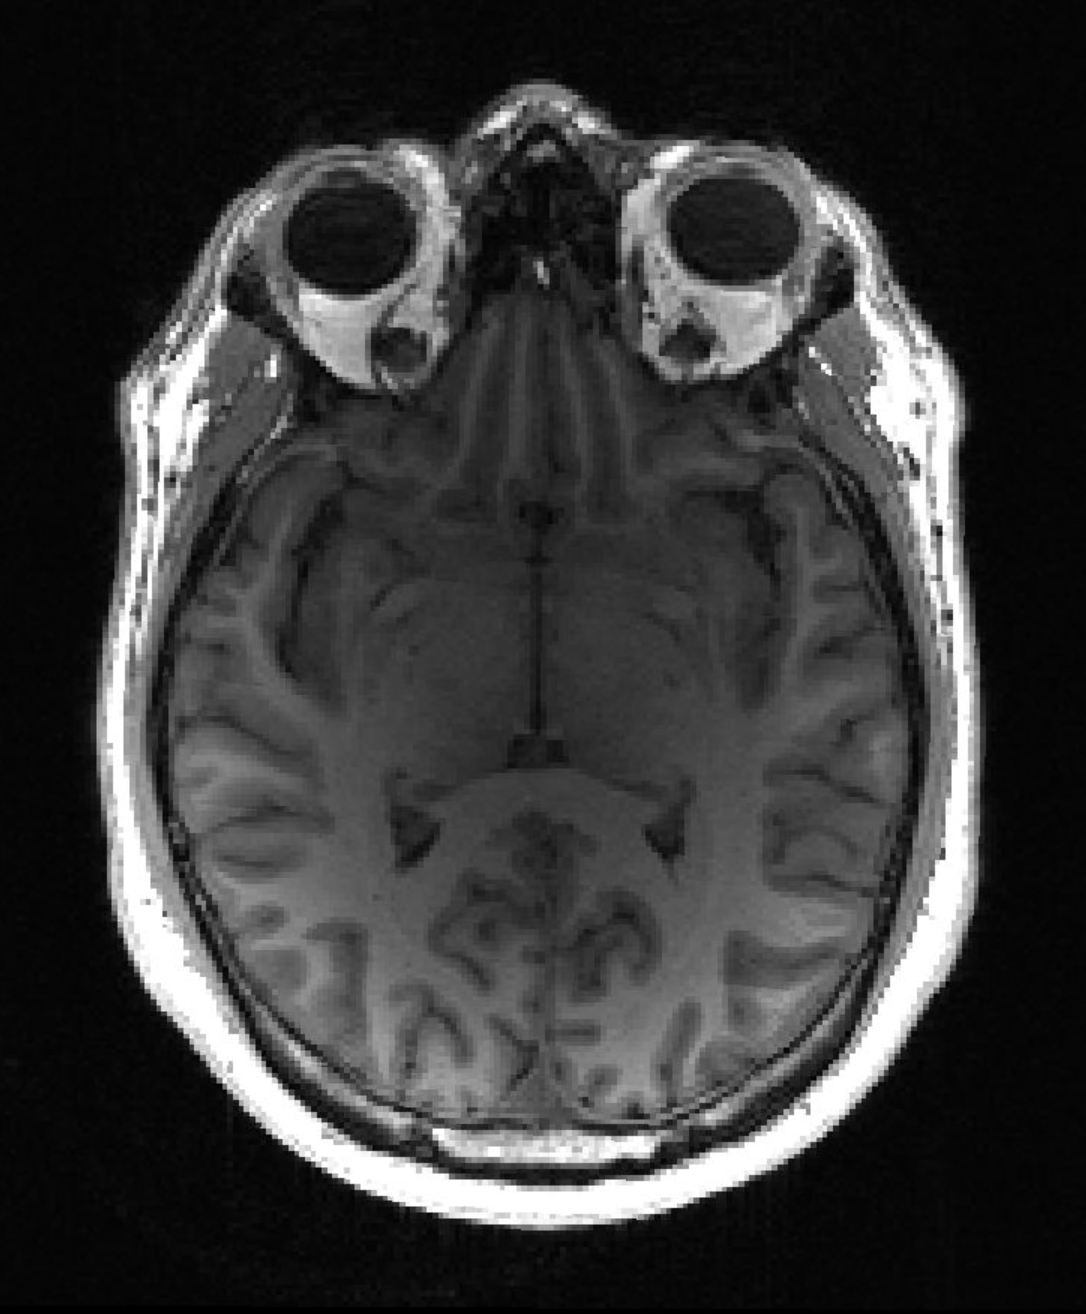

МРТ головного мозга пациента с болезнью Альцгеймера (Источник: Тимоти Риттман)